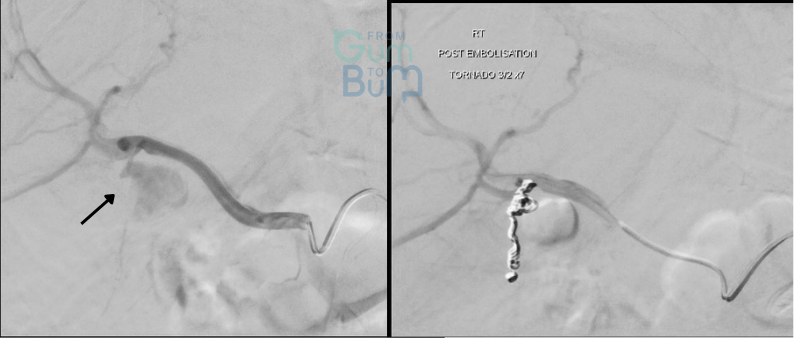

77 yo female comes with severe lower GI bleeding with haemodynamic instability that keeps bleeding and responding only partially to IV Fluids, persisting mildly hypotensive and tachicardic.

She has had a couple of similar episodes in the last year, all were suspected to be due to diverticular haemorrhage in the setting of taking Apixaban for AF but never studied.   A new CT angio suggests blood content in proximal left colon with multiple pancolonic diverticular orifices but no clear bleeding point and no other abnormalities. She is still passing some blood quantity but this has reduced.

Which next step  would NOT be recommended